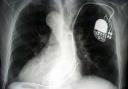

Herzschrittmacher im Einsatz

medicalpicture stellt eine neue Bilderserie zum Thema ‘Herzschrittmacher’ vor. Neue

Illustrationen und Röntgenbilder zeigen die Funktion eines Schrittmachers beim

Menschen.

Ein Herzschrittmacher ist ein Gerät, das in regelmäßiger Abfolge einen

elektrischen Impuls abgibt. Dieses Gerät wird von einer Batterie betrieben, die

mit dem Steuerungssystem fest verbunden ist und nicht gesondert ausgewechselt

werden kann. Die Geräte sind im Laufe der technischen Entwicklung immer kleiner

geworden und haben inzwischen die Größe eines Streichholzbriefchens erreicht.

Dennoch kann der Schrittmacher nicht direkt in das Herz eingesetzt werden.

Vielmehr wird er unterhalb des Schlüsselbeins unter die Haut oder unter einen

Muskel eingebracht und der elektrische Impuls über extrem bewegliche

Kabelsysteme, die Schrittmachersonden, dort hingeleitet, wo die Taktgebung das

Leitungssystem des Herzens erreichen soll. Die Sonden werden über Blutgefäße

direkt in die rechten Herzhöhlen geführt.